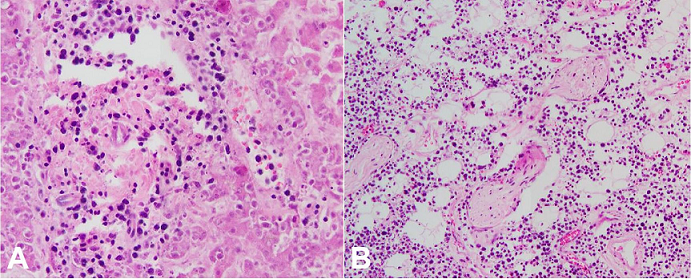

Microscopic examination of the heart, kidneys, perinephric fat and lungs, demonstrated an infiltrate of large, pleomorphic lymphocytes with scattered associated apoptotic debris ( Figures 3- 5). The liver, adrenal glands and periadrenal fat, and a small bowel plaque were also involved by this same infiltrate ( Figure 6).

While areas suggestive of a cellular infiltrate were identified in the spleen, particularly in a perivascular location, the organ was markedly autolyzed, precluding definitive histomorphologic assessment. In the affected tissues, the infiltrating lymphocytes disrupted and focally effaced the normal architecture. There were no germinal centers or follicles appreciated, and overall, the cells were dyscohesive. Of note, variable autolysis affected all sampled tissues. The bone marrow was found to be hypercellular for age, although no definitive areas of cellular infiltrate were identified.

Discernible morphologic features of the infiltrates in all affected organs included the previously mentioned large size, round to oval nuclei with irregular contours, and high nuclear to cytoplasmic ratio. Nucleoli were present in a majority of the neoplastic cells. The findings on hematoxylin- and eosin-stained sections were suggestive of a diffusely infiltrative neoplastic process with intermediate to high grade nuclei, and immunohistochemical stains were performed to further characterize the lymphoid infiltrate. Negative staining for CD3 (T-cell marker) and positive staining for CD20 (B-cell marker) confirmed B-cell lineage ( Figure 7A and 7B). Kappa and Lambda were both negative in the neoplastic cells. A Ki-67 stain was weakly positive in over 50% of the cells of interest ( Figure 7C).